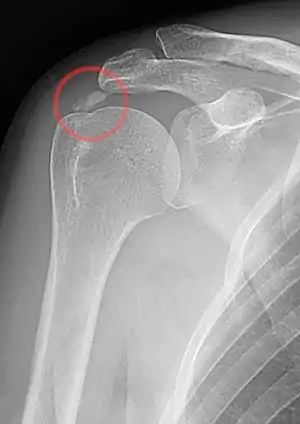

| A plain X ray of the shoulder showing calcific tendinitis | |

The calcific deposits are visible on X-ray as discrete lumps or cloudy areas. The deposits look cloudy on X-ray if they are in the process of reabsorption, and this is also when they cause the most pain. The deposits are crystalline when in their resting phase and like toothpaste in the reabsorptive phase. However, poor correlation exists between the appearance of a calcific deposit on plain X-rays and its consistency on needling. Ultrasound is also useful to depict calcific deposits and closely correlates with the stage of disease.[6]